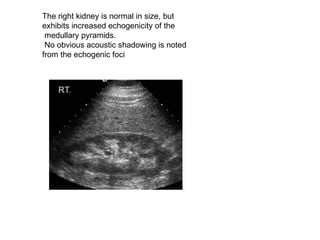

The right kidney is normal in size, but exhibits increased echogenicity of the medullary pyramids. No obvious acoustic shadowing is noted from the echogenic foci